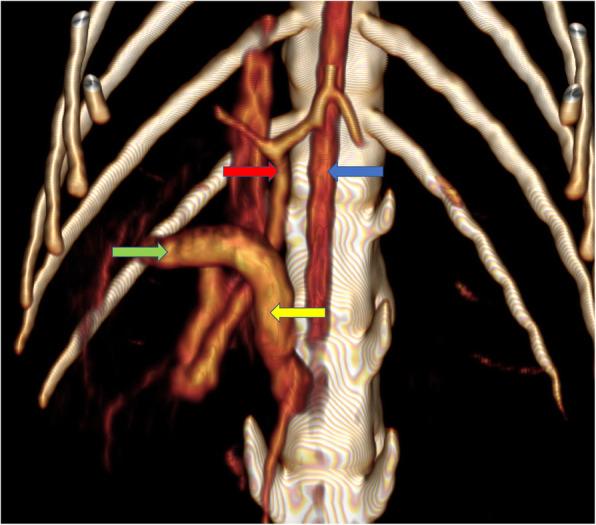

CASE PRESENTATION

An 8-month-old female, domestic cat suffering from chronic diarrhea was referred to the diagnostic imaging unit. The patient showed no other clinical symptoms. An abdominal ultrasonographic examination was performed in order to evaluate the condition of abdominal organs, particularly the gastrointestinal tract. The ultrasound examination showed an ectopic duplex kidney at instead of kidneys in their typical location. Computed tomography (CT) with angiographic phase and excretory urography was requested to evaluate the condition of the kidneys and ureters. The final diagnosis was CFRE, atypical portal vein and coccygeal deformation in an asymptomatic cat with no changes in renal function and normal blood parameters.

CONCLUSIONS

Crossed fused renal ectopia is a rare congenital anomaly and is easily detectable by an abdominal ultrasonographic examination and CT, which allows more complete assessment of both anatomical relations and secretory function of the kidney. The occurrence of CFRE, abnormal portal vein and spinal malformation in a clinically healthy patient is the evidence that congenital malformations may simultaneously involve various, not directly related structures and systems, without significant influence on blood and urine parameters. Thus the most useful tool in the evaluation of the morphological and functional changes is the diagnostic imaging, especially contrast enhanced CT. Our results show that renal fusions should be considered in the differential diagnosis of caudal abdominal masses.

病例介绍

一只 8 月龄雌性家猫因慢性腹泻被转诊至影像诊断部门。该猫除腹泻外无其他临床症状。进行了腹部超声检查以评估腹部器官,特别是胃肠道的情况。超声检查显示异位双肾盂,而非在其典型位置的双肾。为评估肾脏和输尿管的情况,请求进行 CT 增强扫描和排泄性尿路造影。最终诊断为 CFRE、非典型门静脉和尾骨畸形,无症状猫无肾功能和血液参数变化。

结论

交叉融合性异位肾是一种罕见的先天性异常,腹部超声检查和 CT 很容易检测到,这允许对肾脏的解剖关系和分泌功能进行更全面的评估。在临床健康的患者中同时发生 CFRE、异常门静脉和脊柱畸形的情况表明,先天性畸形可能同时涉及多个不直接相关的结构和系统,而对血液和尿液参数无明显影响。因此,评估形态和功能变化最有用的工具是影像学诊断,特别是增强 CT。我们的结果表明,在鉴别诊断尾部腹部肿块时应考虑肾融合。